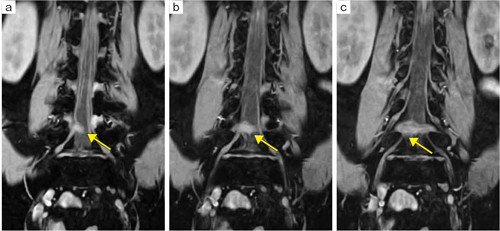

■症例2:神経根MRI画像(Level2のMRI検査)

58歳,男性。腰椎椎間板ヘルニアによる右坐骨神経痛。L4/5レベルのヘルニアにより右L5神経根の圧迫が認められる(←)。

a,b,c:RFスポイルドグラディエントエコー(日立:RSSG),COR 3D MPR像, FOV:384mm,TR/TE:18/9.2,FA:10°,Thickness:1.5mm